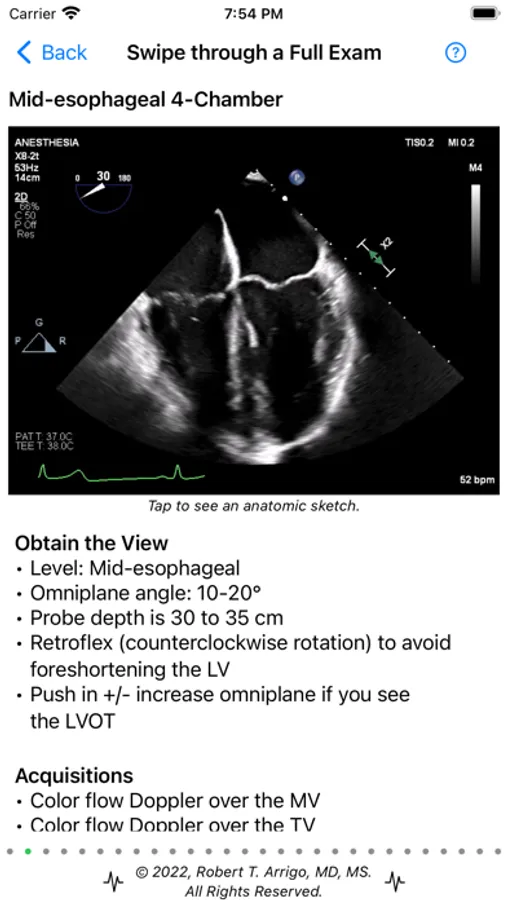

About ECHO On

ECHO On is a free medical education resource for learning Transesophageal Echocardiography including a free, enlarging question bank, a Rescue TEE cognitive aid, a Case Log system for submission to the NBE, and a growing perioperative Quick Reference library with offline echo loops that work even in the OR without internet access, and includes pathology examples, techniques, and normal loops of the heart. ECHO On will walk you through an entire standard 28 view exam teaching you the anatomy, function and Doppler interrogations you should perform at each view, and how to interpret them.

ECHO On Screenshots